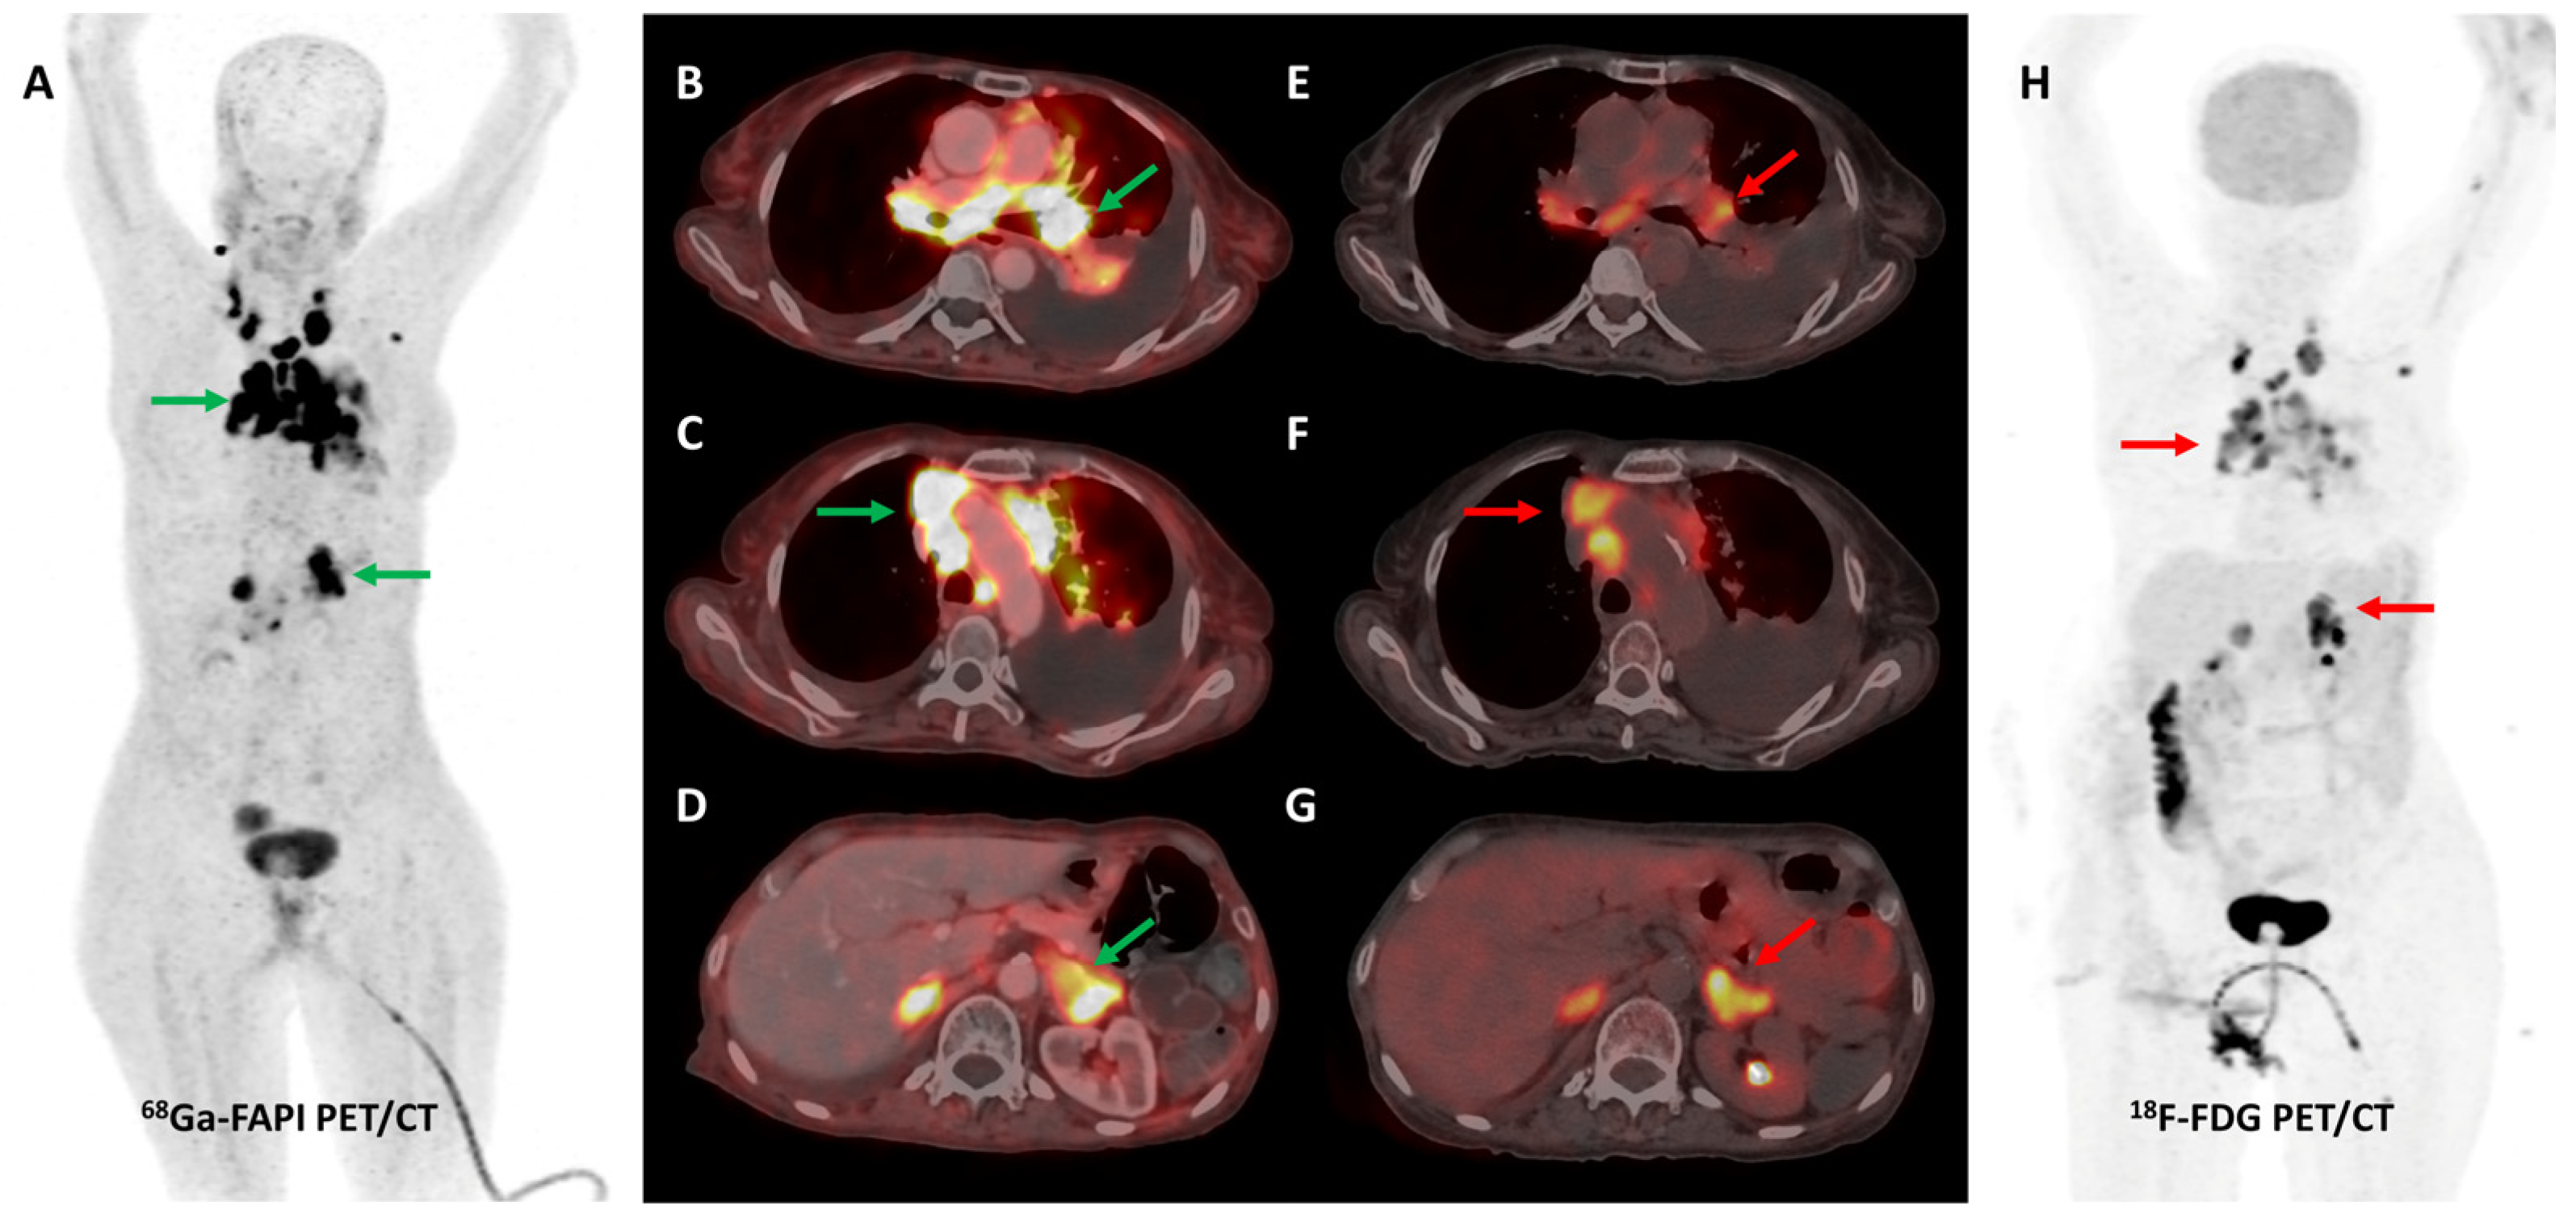

Loktev et al. conducted a proof-of-concept study in 2018 where they first demonstrated high lesional tracer uptake in three patients with breast, lung, and pancreatic cancers on FAPI PET imaging [24]. Subsequently, the same group from Heidelberg reported [68Ga]Ga-FAPI-04 PET/CT results of 80 patients with 28 different tumor types. The degree of tracer uptake differed significantly among tumor types, being highest in sarcoma, cholangiocarcinoma, esophageal, breast, and lung cancer [51]. Few other basket trials evaluated FAPI PET/CT in heterogeneous, oncological patient cohorts. The most consistent advantage of FAPI over FDG across these studies was easier lesion detection owing to a significantly lower background signal, with resultant higher target-to-background ratios (TBRs) and sharp image contrast [52]. One such example is presented in Figure 2.

Figure 2.

[68Ga]Ga-FAPI-04 and FDG PET/CT images in a 59-year-old woman with biopsy-proven metastatic left lung adenocarcinoma. [68Ga]Ga-FAPI-04 PET/CT images revealed intensely tracer avid left hilar mass lesion ((B)—green arrow), multiple enlarged mediastinal ((A,C)—green arrows) lymph nodes, and bilateral adrenal metastases ((A,D)—green arrows depicting left adrenal lesion). Additionally, moderate left-sided pleural effusion with associated left lung lower lobe collapse was noted. Overall, FAPI PET/CT demonstrated higher tracer avidity and TBRs than FDG PET/CT ((E–H)—red arrows).